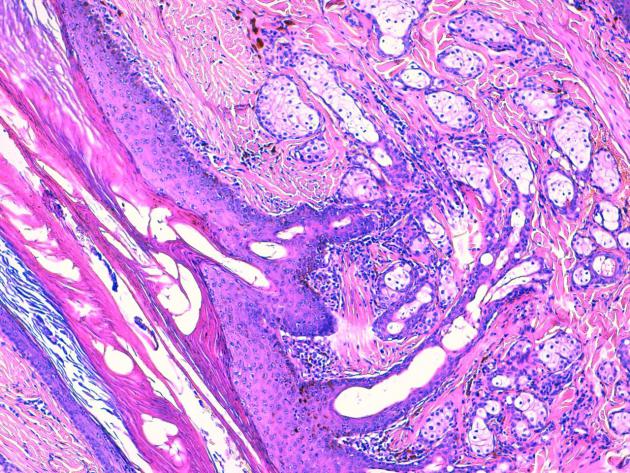

La plupart révèlent un épiderme hyperplasique auquel s’abouchent des infundibula folliculaires évasés, hyperkératosiques, auxquels sont annexées de nombreuses glandes sébacées, plurilobulées, hyperplasiques, via des canaux sébacés dilatés et multiples. Au sein des unités folliculaires, les follicules pileux montrent une portion profonde rudimentaire souvent sous la forme d’un bulbe isolé et malformé. Les glandes sudorales épitrichiales sont rares et de petites taille dans le derme profond.

| Fig 3 : Hamartome sébacé de Jadassohn : de multiples glandes sébacées plurilobulées, ramifiées et matures, s’abouchent à un même infundibulum folliculaire béant, via des canaux sébacés (H&E, X 25). | |

| Fig 4 : Hamartome sébacé de Jadassohn : de multiples glandes sébacées plurilobulées, ramifiées et matures, s’abouchent à un même infundibulum folliculaire béant, via des canaux sébacés (H&E, X100) | |